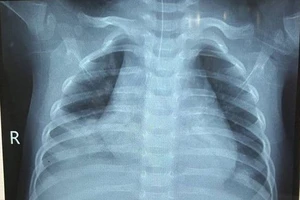

Chiều 17-4, Bệnh viện Nhi Thanh Hóa cho biết vừa tiếp nhận một bệnh nhi 20 tháng tuổi nhập viện trong tình trạng ho nhiều, khó thở, suy hô hấp.

Theo các bác sĩ, rất may là trường hợp trẻ uống dầu hỏa này được phát hiện sớm và nhập viện kịp thời điều trị. Hiện tình trạng trẻ ổn định, tiếp tục được theo dõi, điều trị theo phác đồ.